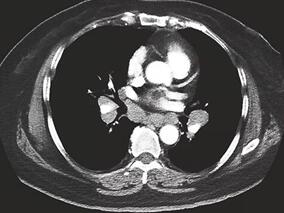

1小时条评论【病例资料】 患者,女性,40岁,北京市干部。因四肢麻木、无力2个月余于1995年7月18日收入院。 现病史:患者于1995年5月无明显原因发热,体温约38.5℃,按上呼吸道感染治疗后体温恢复正常。2周后出现四肢麻木、无力,无明显疼痛,于外院就诊,诊断为周围神经病变...